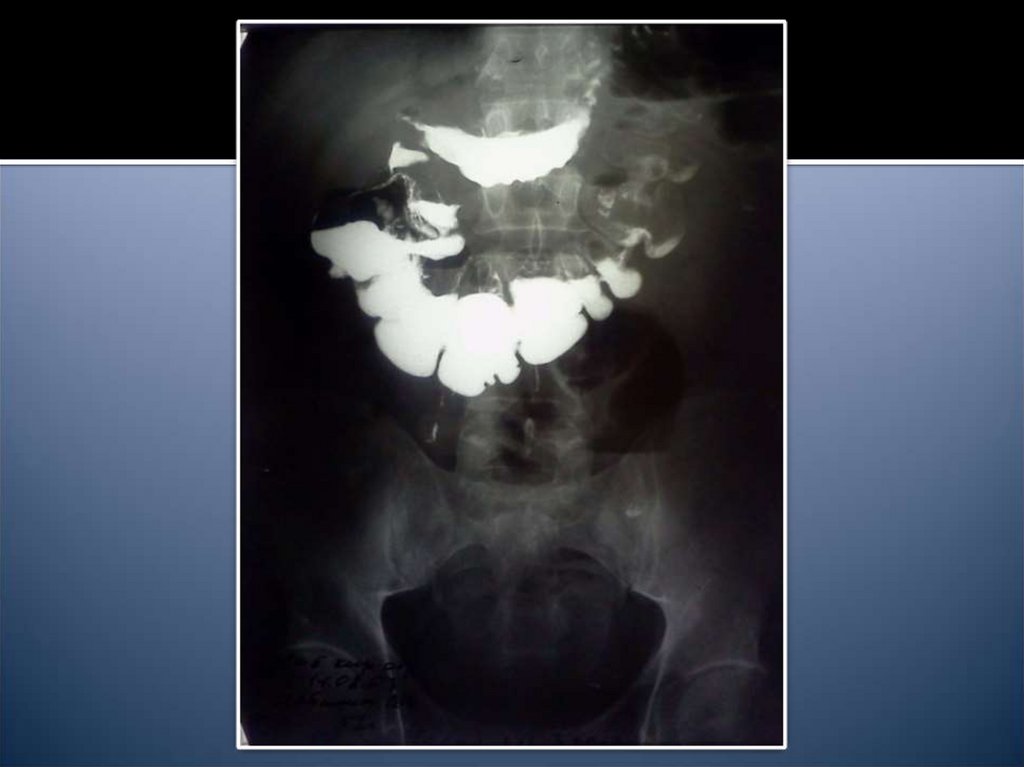

14. Рентгенологические признаки

Чаши Клойбера

Симптом Кивуля (аркады)

Проба Шварца

Пневматоз петель кишечника